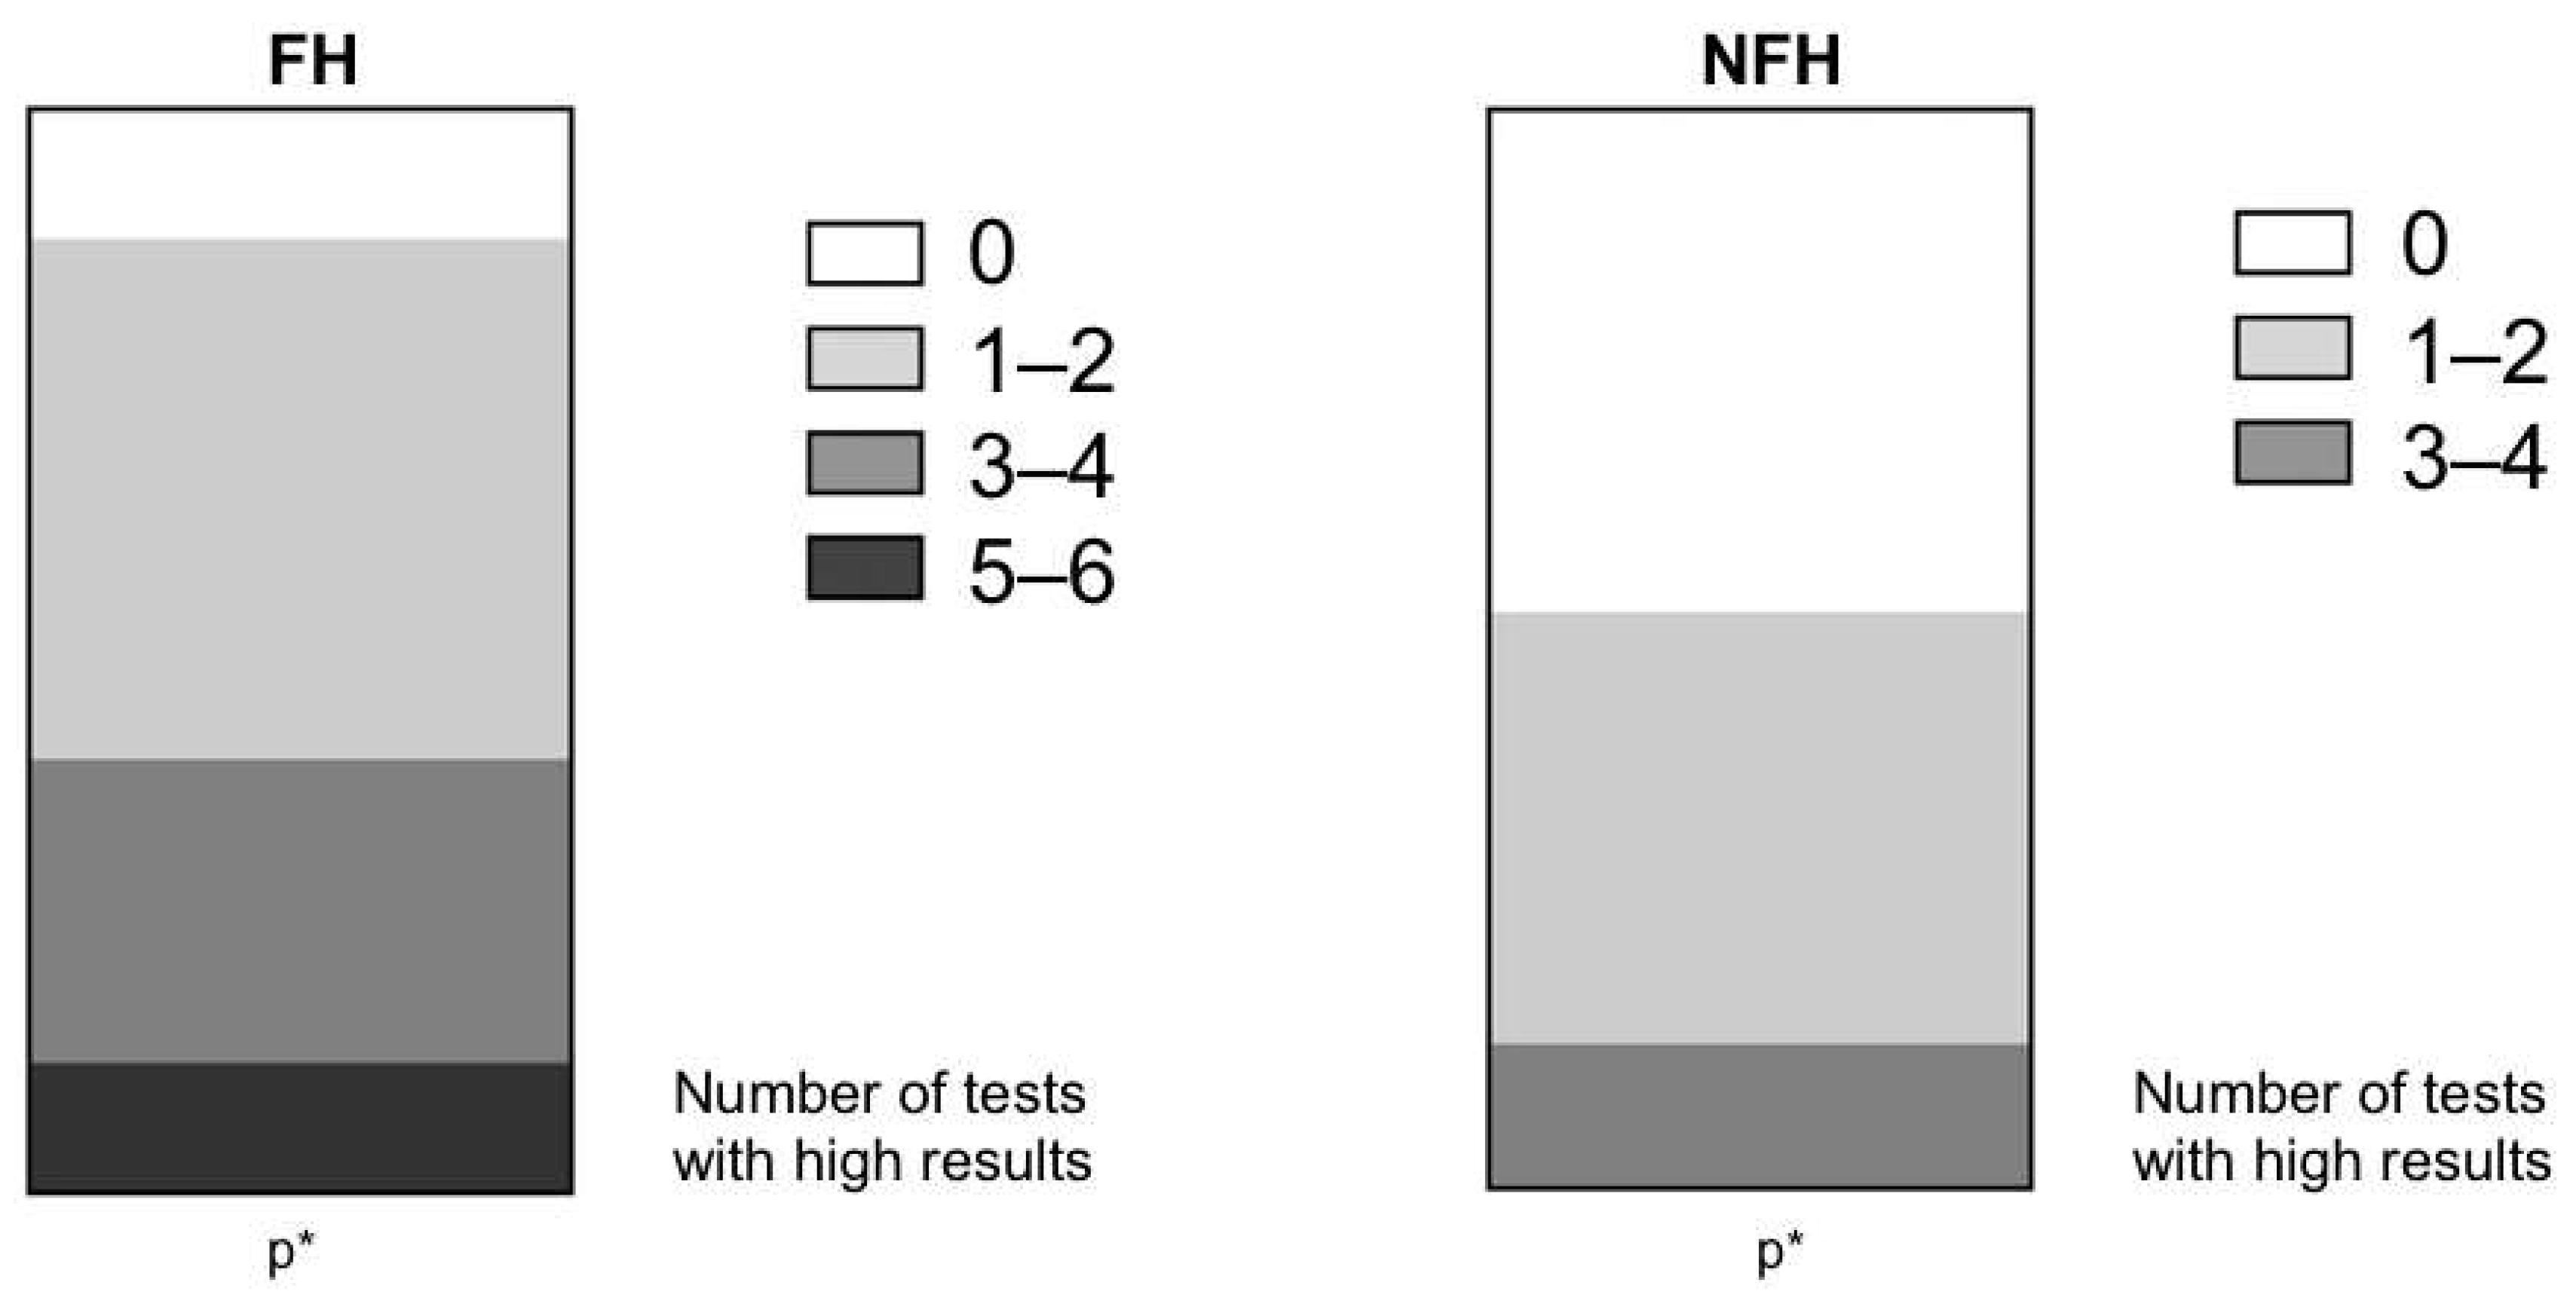

| Proportion of High Atherosclerosis Results (%) | FH (n = 60) | NFH (n = 30) | p Value |

|---|---|---|---|

| dAWAI | 48.3 (29/60) | 6.7 (1/30) | <0.001 |

| aAWAI | 46.7 (28/60) | 6.7 (2/30) | <0.001 |

| cIMT | 38.0 (23/60) | 23.3(7/39) | ns |

| TCSdsc | 25.0 (15/60) | 26.7 (8/30) | ns |

| TCSacs | 41.7 (25/60) | 16.7 (5/30) | <0.001 |

| CCS | 36.7 (22/60) | 26.7 (8/30) | ns |